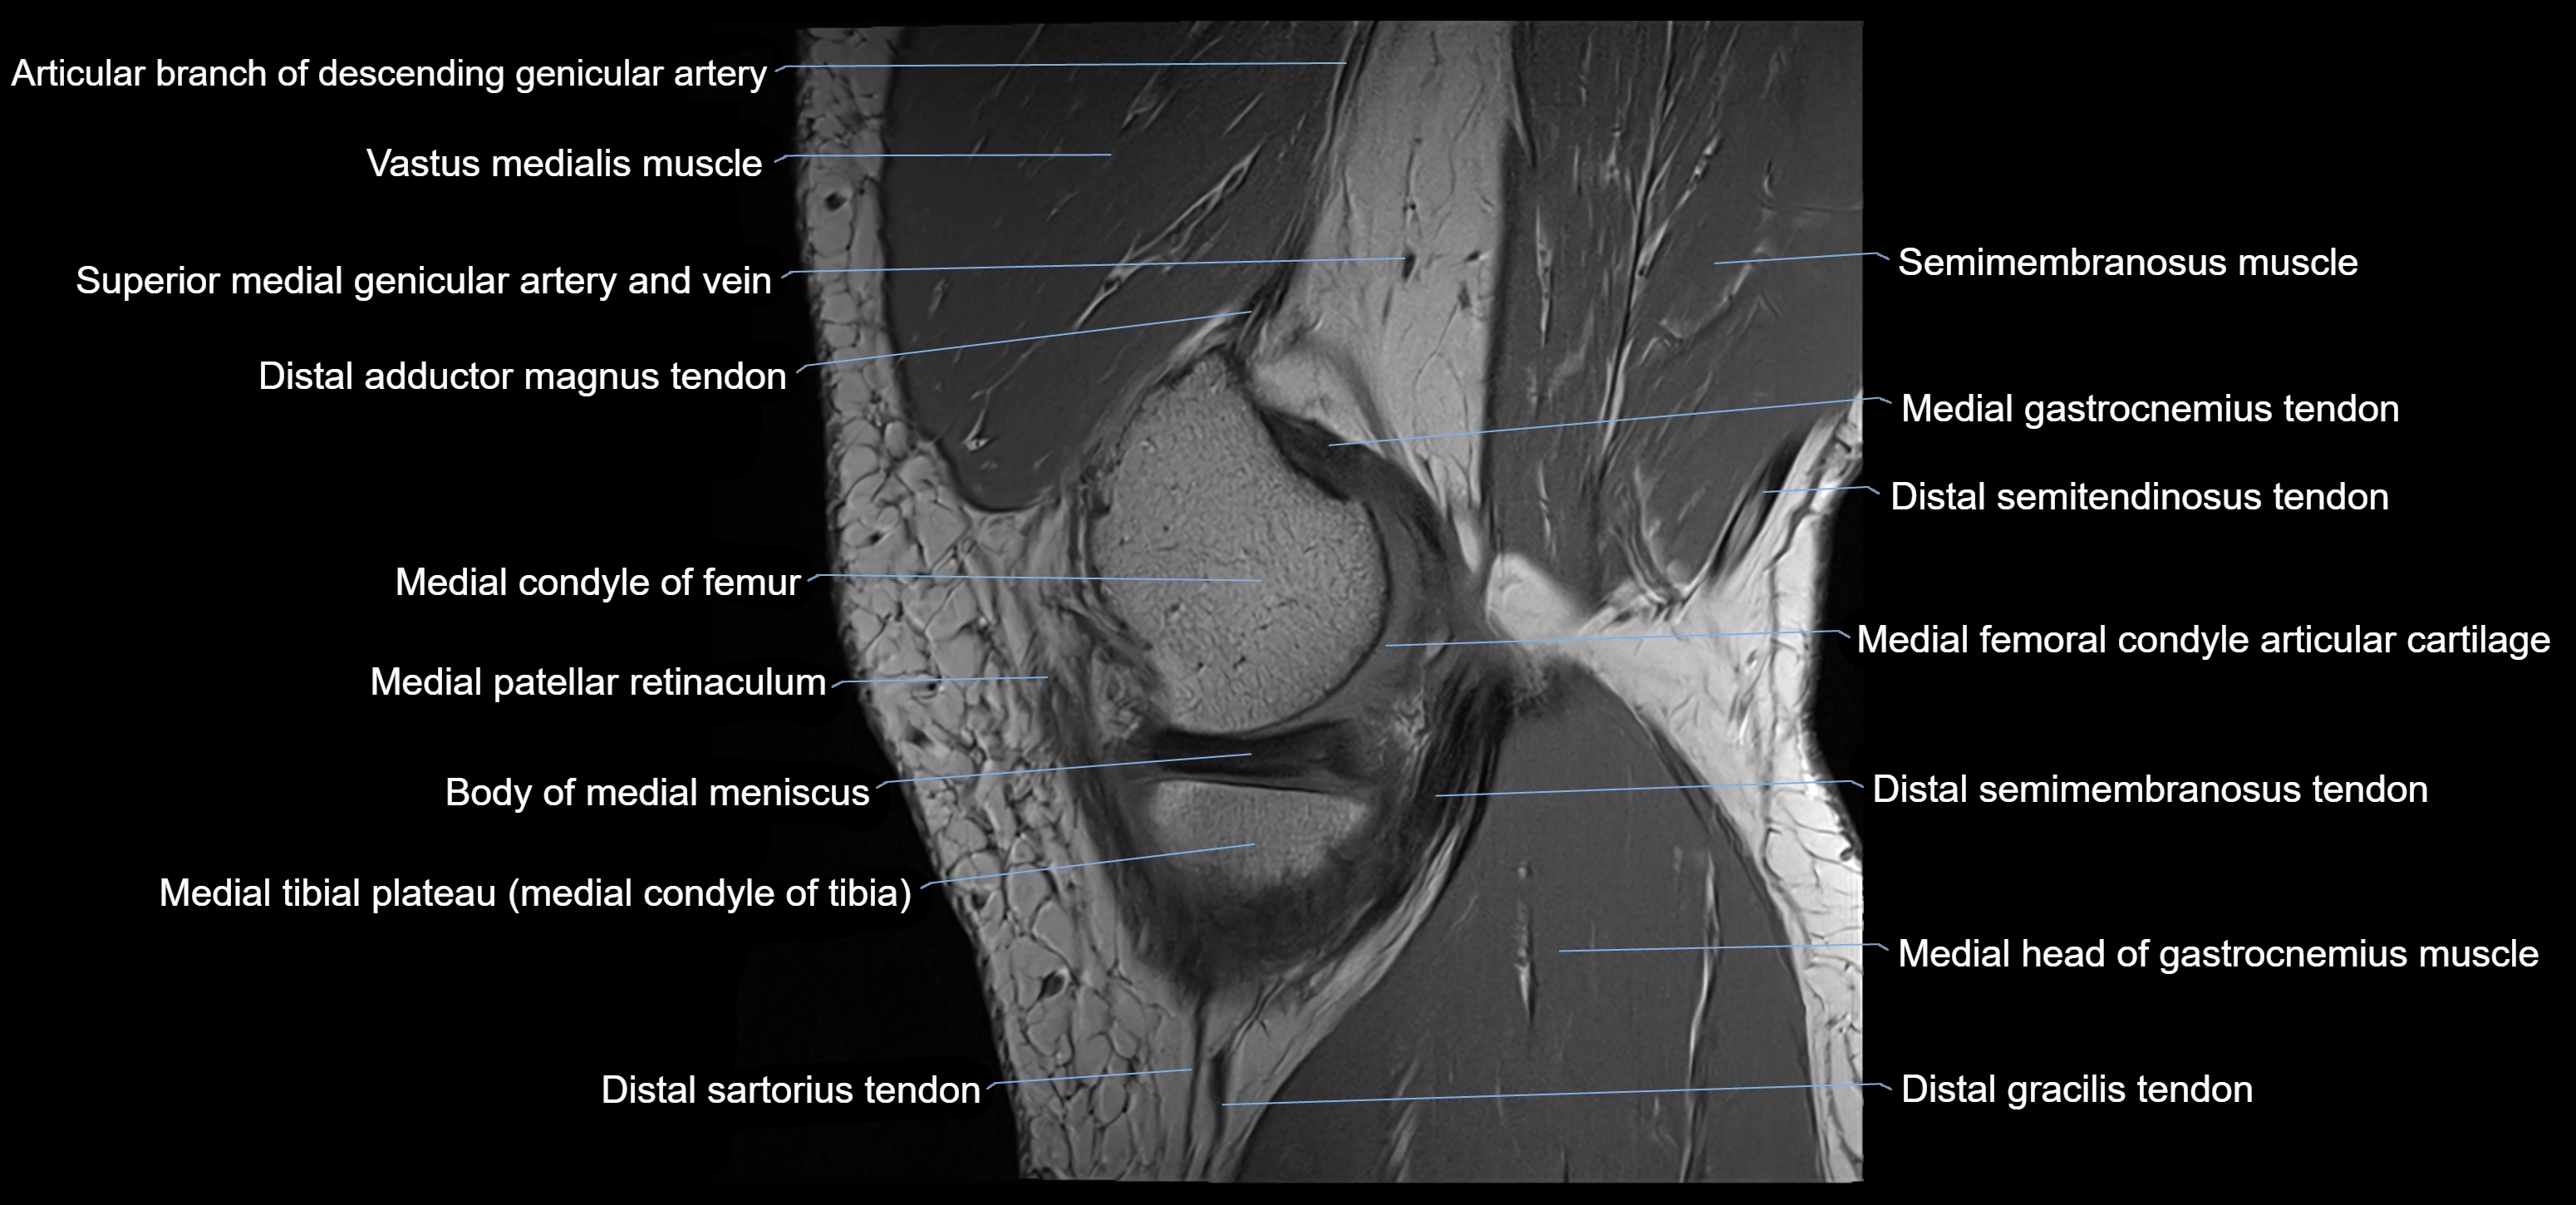

- Body of medial meniscus

- Distal adductor magnus tendon

- Distal semimembranosus tendon

- Distal semitendinosus tendon

- Gracilis tendon (Distal)

- Medial condyle of femur

- Medial condyle of tibia

- Medial gastrocnemius tendon

- Medial head of gastrocnemius muscle

- Medial patellar retinaculum

- Medial tibial plateau

- Semimembranosus muscle

- Superior medial genicular artery

- Vastus medialis muscle